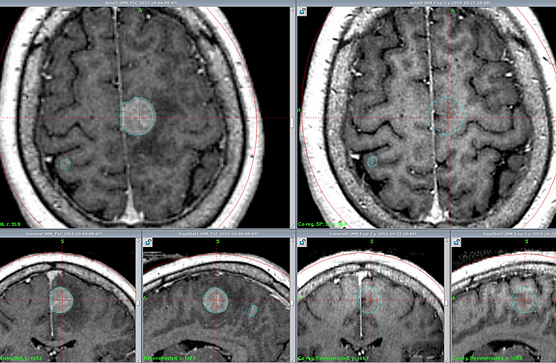

КТ-симуляция является ключевым этапом в подготовке к лучевой терапии, позволяющим получить детальные трёхмерные изображения области лечения в том же положении, в котором будет проходить ежедневное облучение.

- Процесс КТ-симуляции: Пациент располагается на столе компьютерного томографа в индивидуальной иммобилизирующей маске. Выполняется серия КТ-сканов, охватывающих первичную опухоль, зоны регионарного лимфооттока и окружающие здоровые ткани. Часто используются контрастные вещества для лучшей визуализации опухоли и сосудов.

- Маркировка: На коже пациента или на маске наносятся временные или постоянные метки (татуировки в виде точек) для точного воспроизведения положения при ежедневном облучении.

- Сбор данных: Полученные КТ-изображения передаются в специализированную систему планирования лучевой терапии.

Эти данные служат основой для точного контурирования целевых объёмов и критических органов, а также для последующего дозиметрического расчёта.